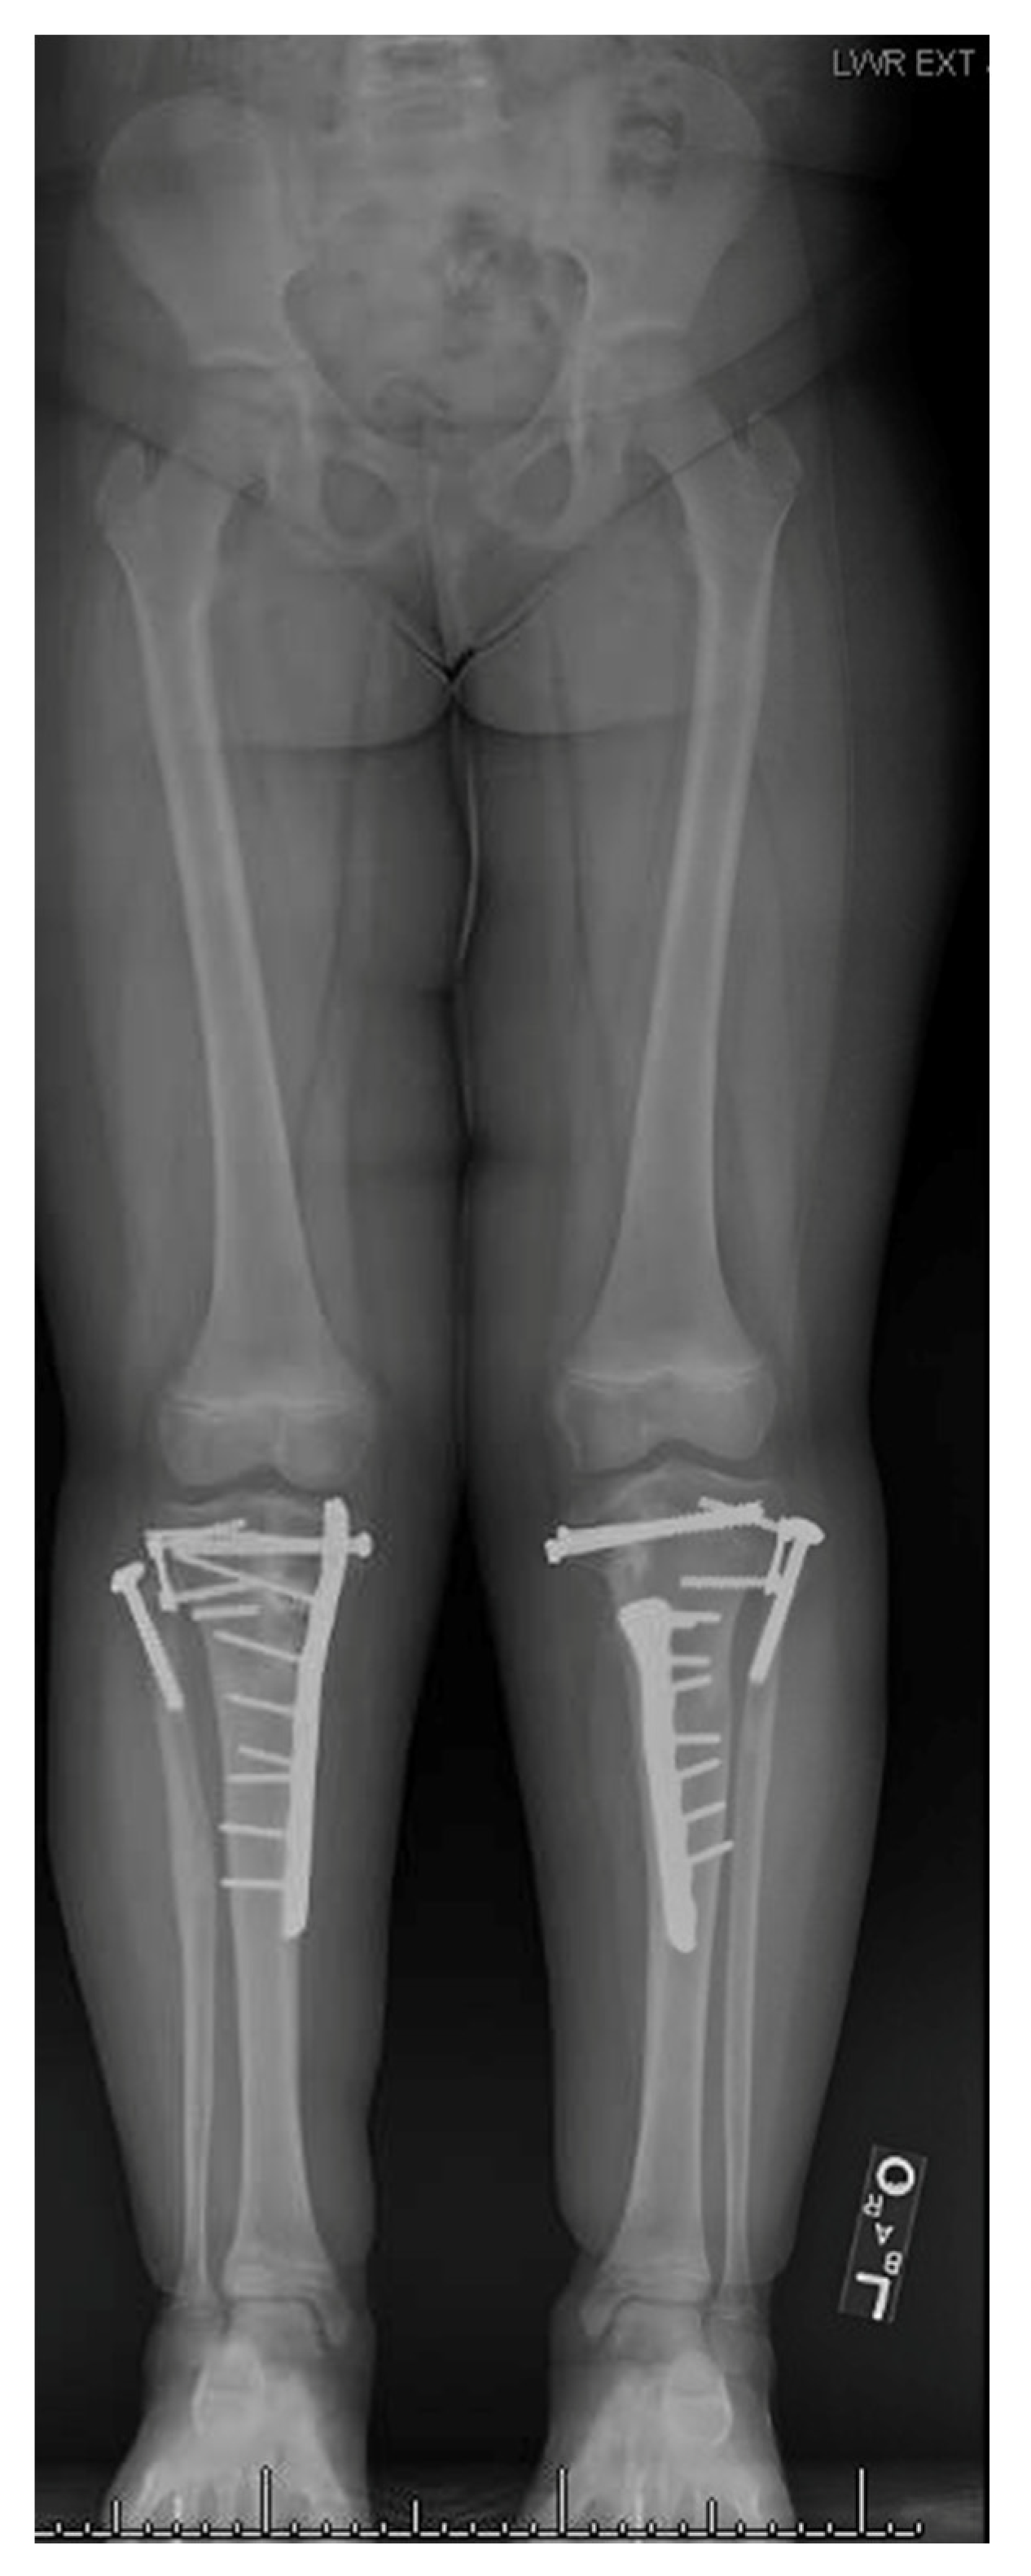

13. Osteotomies with Acute Correction

14. Hemi-Plateau Elevation Osteotomy

15. Combined Osteotomies

17. Gradual Correction with External Fixation